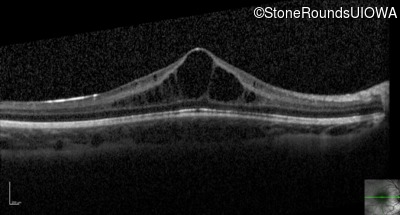

Optical Coherence Tomography - Left - 20/40

Exemplar / OCT Stack